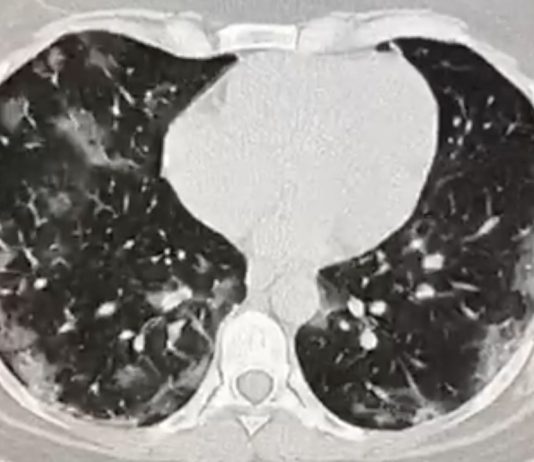

Dipartimento dei Servizi Sanitari - U.O. Radiologia – ASP Vibo ValentiaMaschio, 47 anni. Anamnesi patologica remota muta.

Il paziente giunge tramite 118 il 29/3 in...